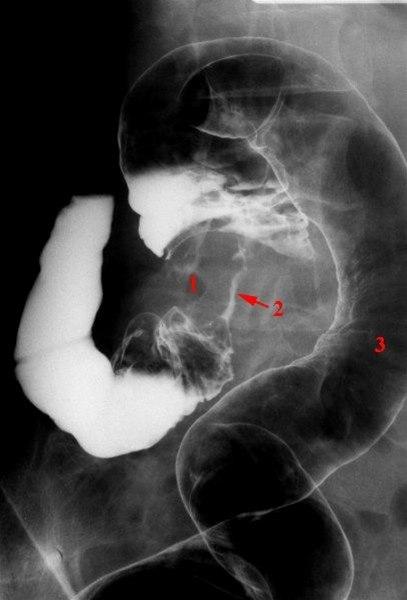

Dobbel kontrast teknikk

1. Stenoserende tumor i sigmoideum

2. Kontrast i trangt lumen gjennom tumor

3. Normal del av sigmoideum